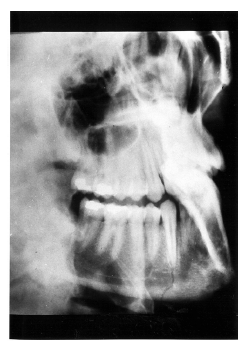

Figure 7 - Extensive Loss of Alveolar Bone

Figure 7

Figure 7 illustrates severe periodontal disease with extensive loss of alveolar bone around the tooth.